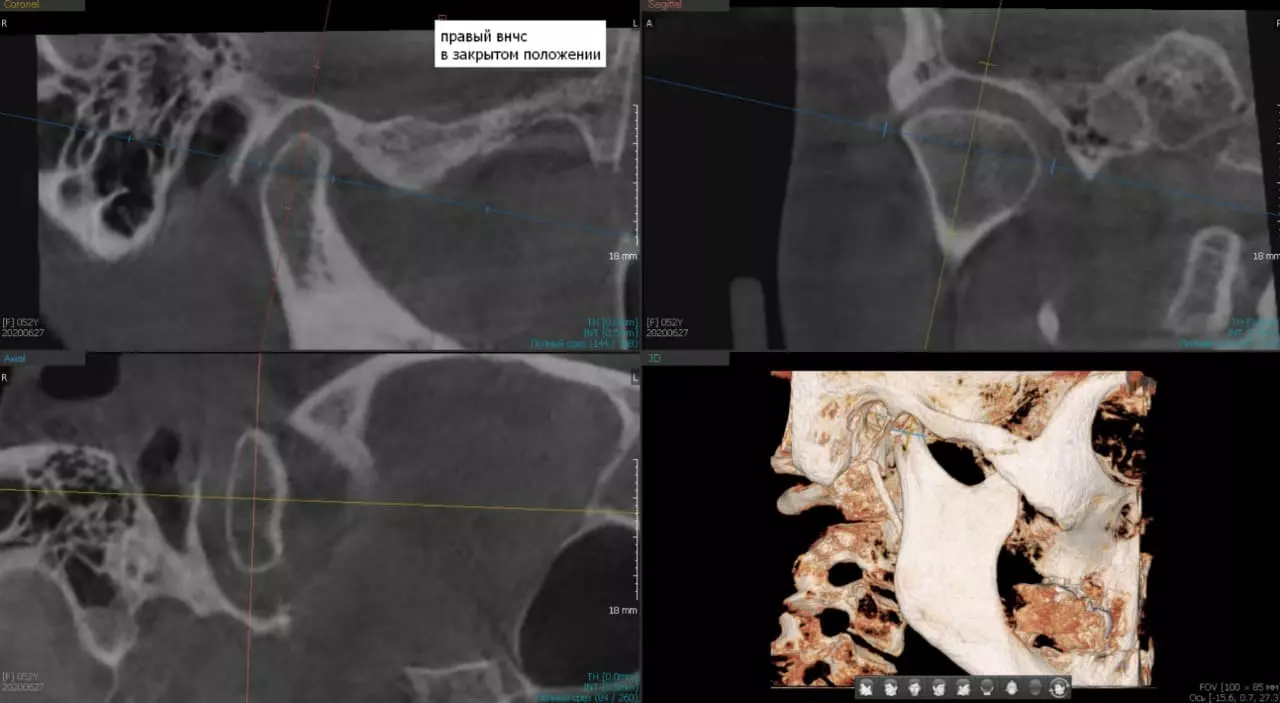

Еще одним важным преимуществом КТ является возможность получения изображений в различных плоскостях – аксиальной‚ сагиттальной и корональной. Это позволяет врачу оценить пространственные взаимоотношения между зубами‚ костью и окружающими тканями‚ что крайне важно при планировании имплантации‚ сложных ортодонтических процедур или хирургических вмешательств.